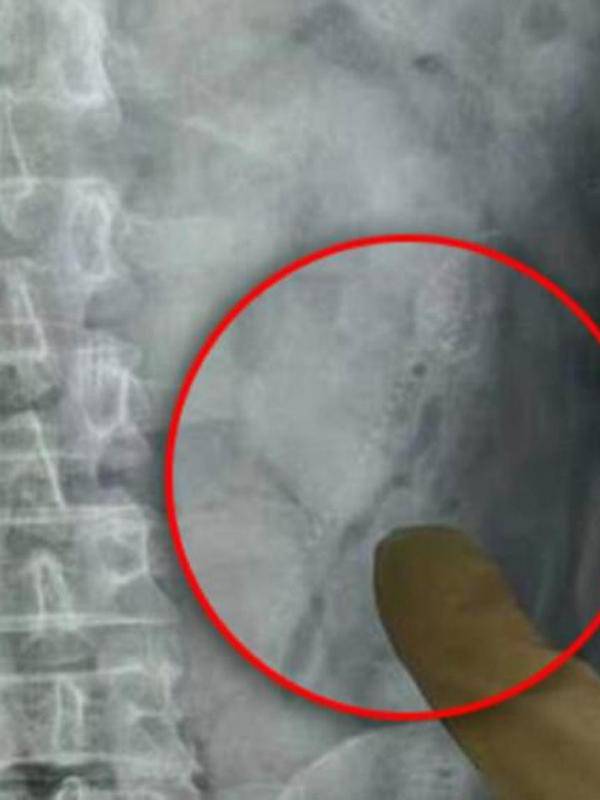

Setelah dironsen, terkuaklah kalau dua ikan telah berada di dalam tubuhnya selama lebih dari 24 jam. Ahli bedah pun melakukan radiografi digital perut untuk mencari ikan tersebut.

Pasien didiagnosis dengan perforasi usus dan berisiko septic shock karena infeksi. Untungnya, dokter berhasil mengeluarkan salah satu ikan yang panjangnya 15 sentimter.

Namun, mereka tidak berhasil menemukan ikan kedua meski mengidentifikasi luka pada dinding usus. Setelah ditilik lebih lanjut, ikan kedua ternyata terjebak di bagian kiri atas perutnya.

"Ikan kedua panjangnya 13 sentimeter. Ia bisa saja kehilangan nyawanya jika ikan itu berenang lebih jauh dan mencapai organ bagian atas," jelas dokter di rumah sakit tersebut.